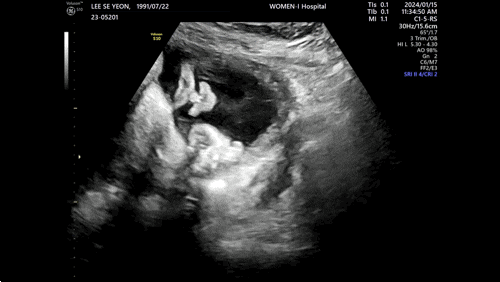

임신기록 ~34주

#태동 꼬물꼬물 새벽에는 좀 자자....미뇽아? 딸꾹질도 많이 함 ㅠㅠ #33주 #아기빨래 손수건50장 결국 ...

~32주 태동검사 백일해주사